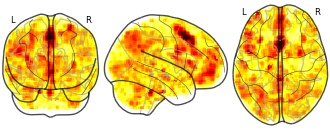

Whole-brain pearson correlations are calculated from a brain-masked, 4mm transformation of the original image with complete-case analysis, meaning only using voxels that are present in both images are used in the calculation. The search is limited to images linked to published papers. Images that are tagged as "thresholded," meaning that the image has less than 25% of coverage for a standard brain mask, are not included in the comparison. Similarly single subject maps, parcellations, atlases and ROI maps are excluded.